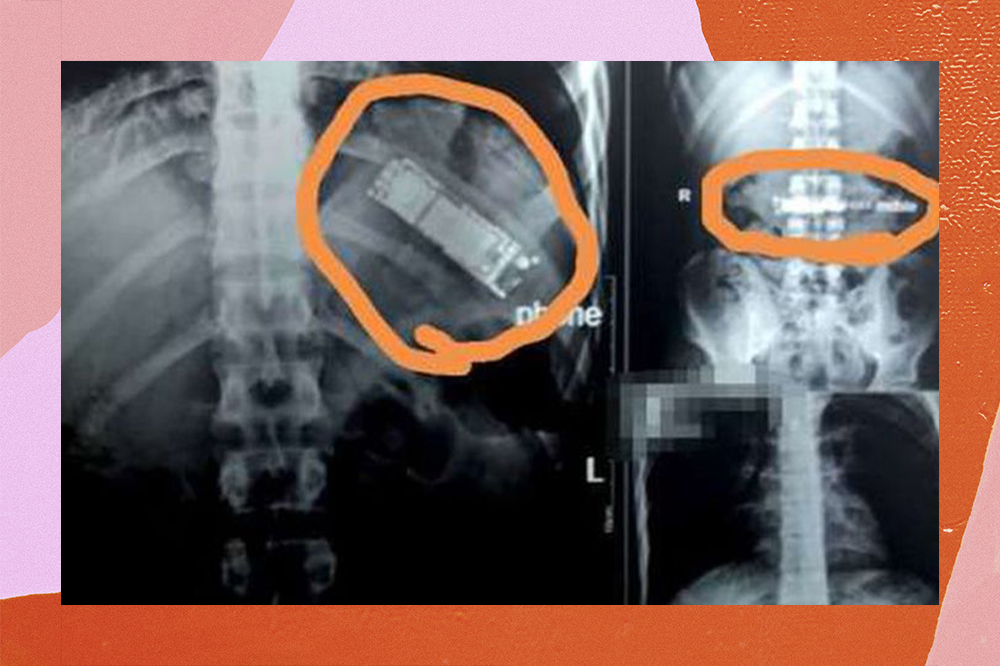

No começo deste ano, um egípcio de 28 anos, morador de Brenha, província ao norte do Cairo, engoliu um celular durante uma brincadeira com os amigos, pensando que seria possível facilmente regurgitá-lo, como afirmou ao jornal local Al Watan. Mas é claro que ele acabou não conseguindo se livrar do aparelho e passou os últimos 7 meses com ele dentro do estômago!

De acordo com o portal de notícias Akhbar Al Youm, o paciente não teria contado sobre o ocorrido para a sua família. Ele, como era de se esperar, começou a ter complicações e foi levado ao hospital. Lá, os médicos detectaram o celular durante um ultrassom e o rapaz precisou passar por uma cirurgia de emergência.

O cirurgião, Mohammed Al Jazar, conta que, assim que a presença do celular foi identificada, “o paciente foi encaminhado às pressas para o departamento de cirurgia geral do hospital”. Ele agora passa bem, mas que sufoco, hein? E, cá entre nós, que papelão do homem que, com 28 anos nas costas, decidiu engolir um telefone por causa de um desafio entre amigos.